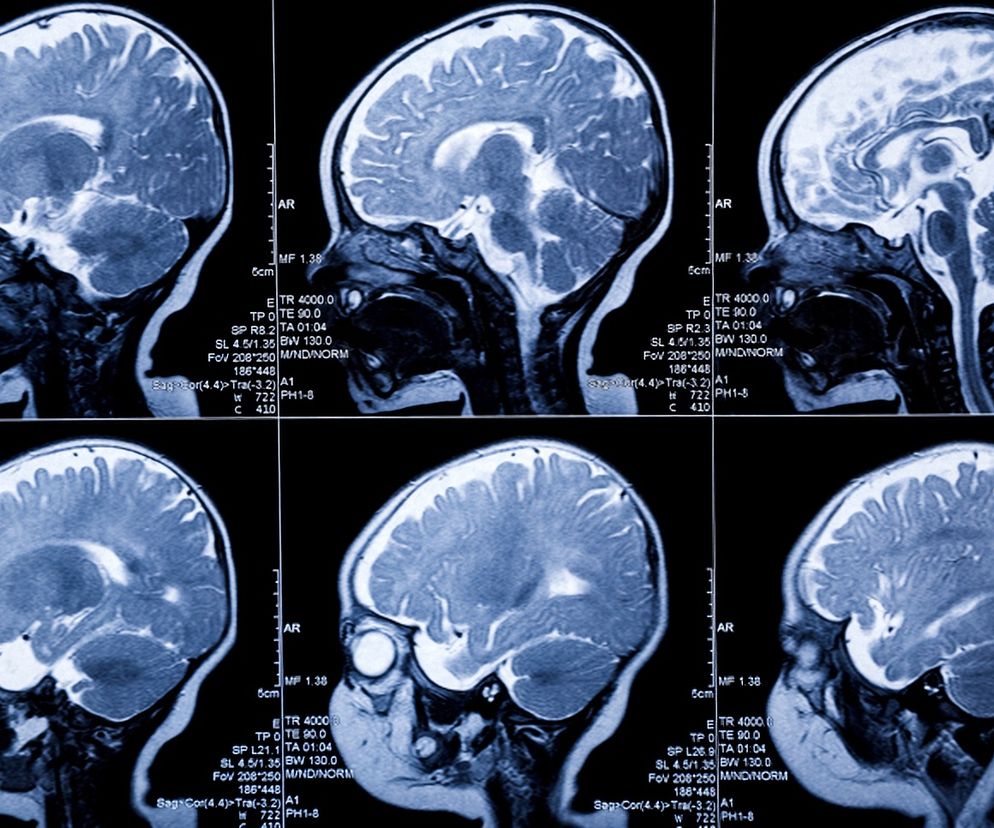

Gruczolak przysadki mózgowej to łagodna zmiana nowotworowa i najczęstsza postać guza przysadki mózgowej. Jakie są przyczyny i objawy gruczolaka przysadki mózgowej? Kiedy można zastosować leczenie farmakologiczne, a kiedy konieczna jest operacja? Jakie badania należy wykonać przy podejrzeniu gruczolaka przysadki mózgowej?

Gruczolak przysadki mózgowej to łagodny guz nowotworowy, który znajduje się w środkowym dole czaszki, w zagłębieniu kości klinowej, tzw. siodle tureckim. Jest on zbudowany m.in. z komórek dokrewnych przedniego płata przysadki mózgowej. Jeśli są to komórki wydzielające substancje aktywne hormonalnie, guz również jest czynny hormonalnie. Są to tzw. gruczolaki wydzielające, wśród których najczęściej występują gruczolaki prolaktynowe (ponad 50%), gruczolaki produkujące hormon wzrostu (15-25%) i gruczolaki kortykotropowe (5%). Pozostałe guzy są nieczynne hormonalnie (gruczolaki niewydzielające).